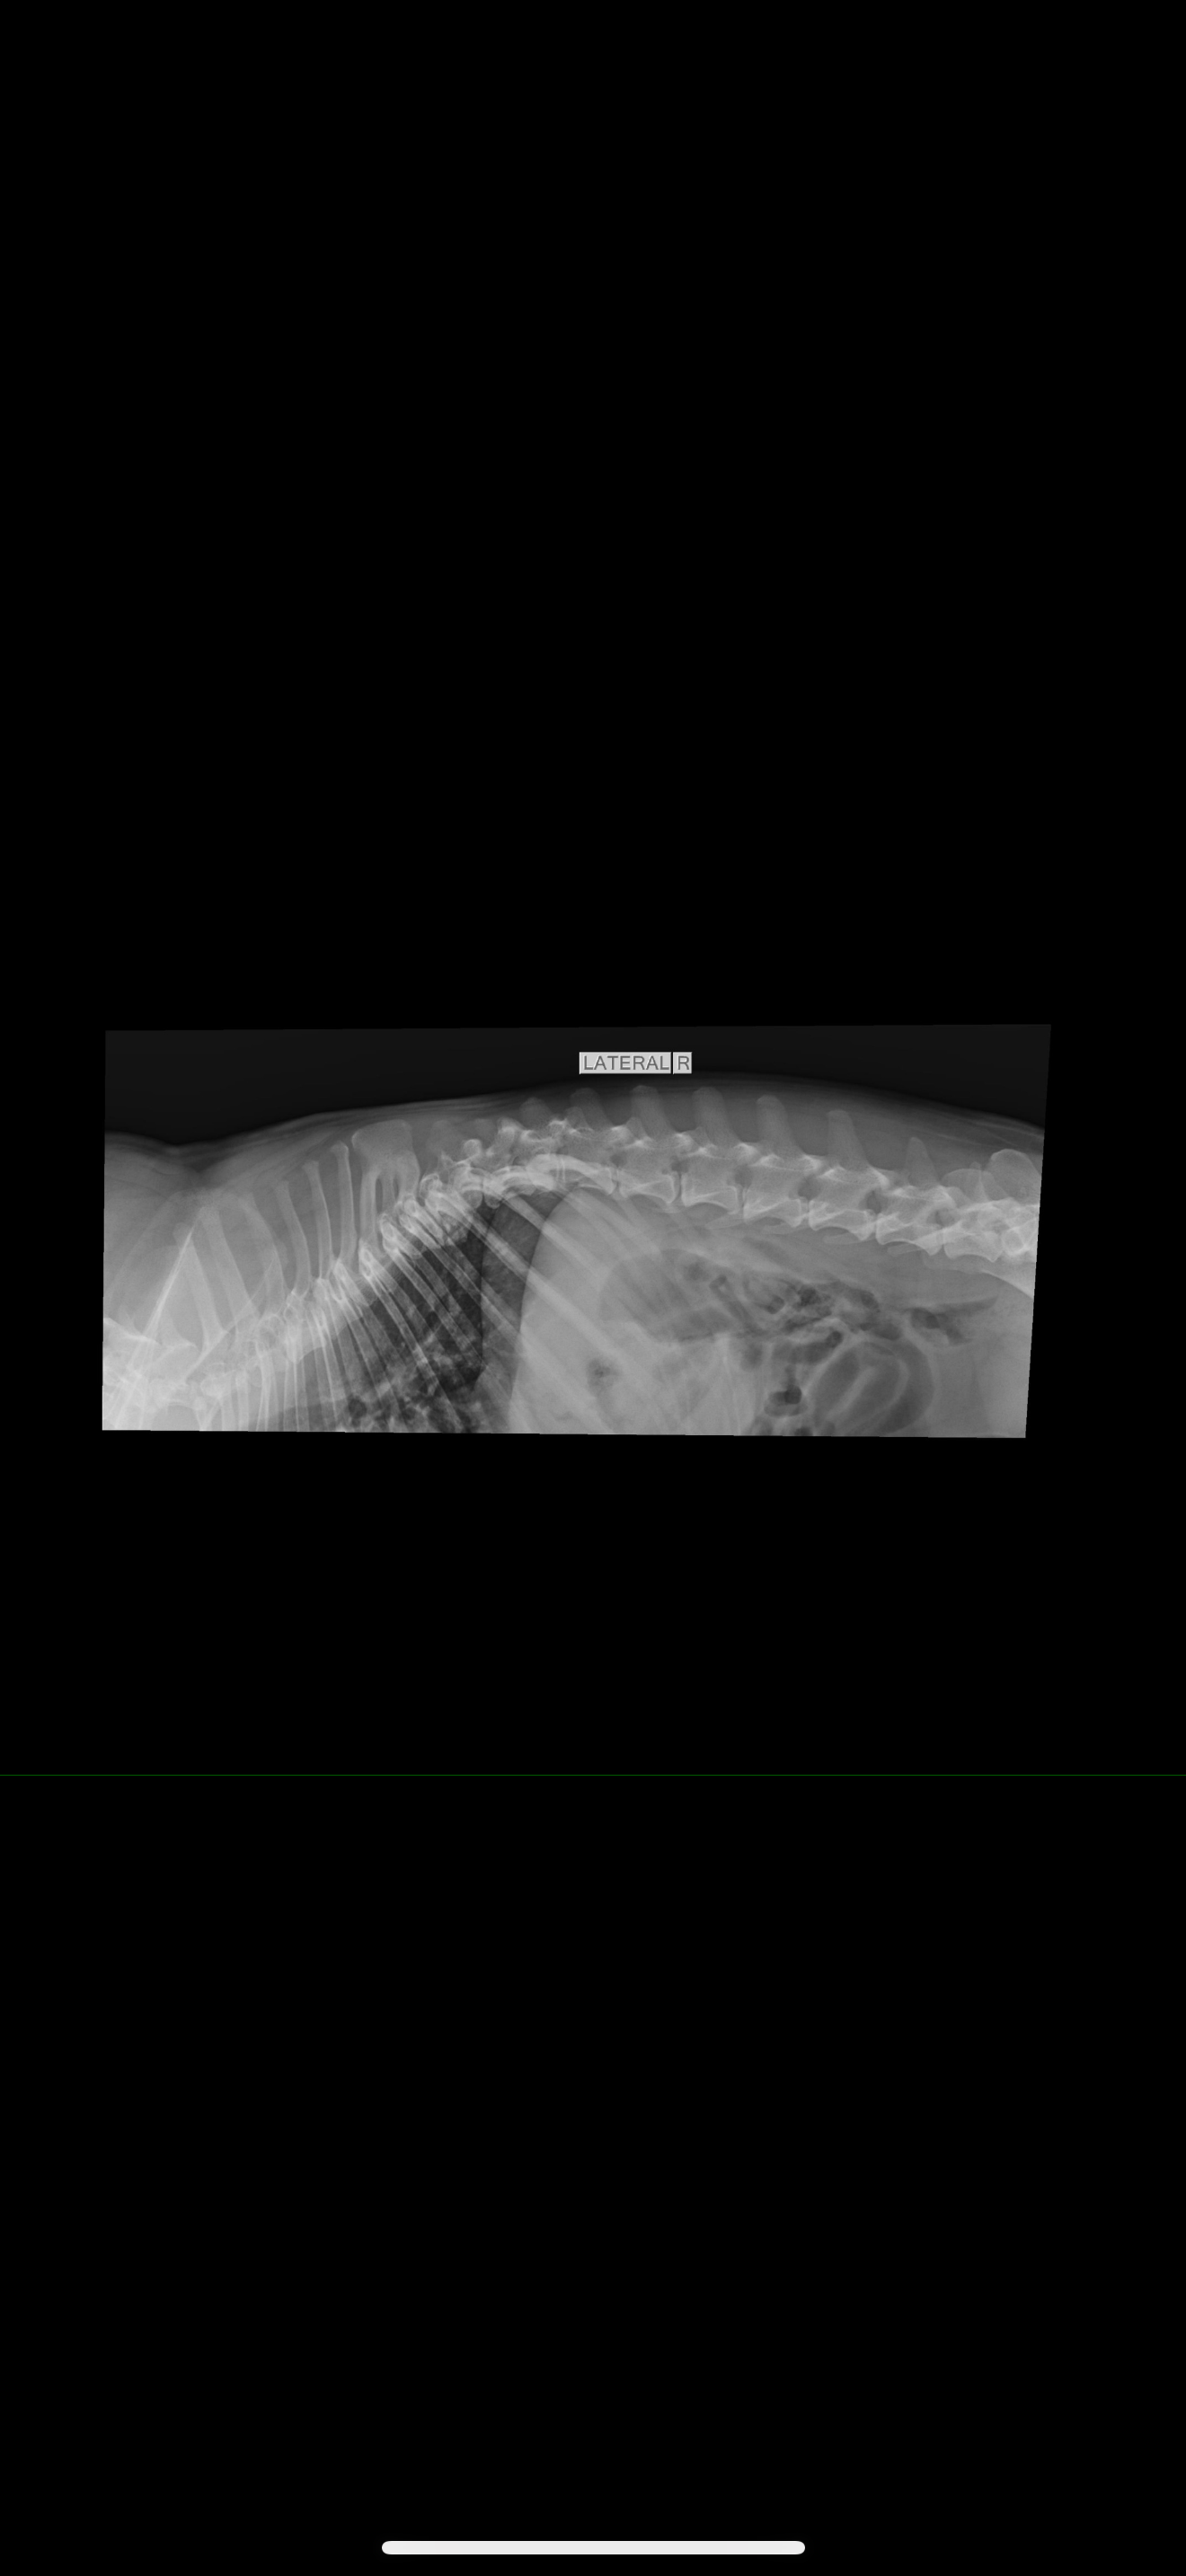

We’re reaching out with heavy hearts to ask for your support for our Moxie girl.A few days ago, she was diagnosed with IVDD (Intervertebral Disc Disease), and our world has been turned upside down. It’s left her paralyzed, and seeing her struggle has been absolutely heartbreaking. If you know Moxie, you know she’s the happiest, silliest, most loving little dog always asking to be held or played with.She’s always been the life of the party ! wiggling, dancing, and greeting everyone who walks through the door like they’re her favorite person in the world.We’ve been told that an MRI and surgery are her best chances to regain mobility and live the happy, full life she deserves. Unfortunately, the cost of these procedures is more than we can manage on our own. We’re doing everything we can, but we need a little help to give her this chance.